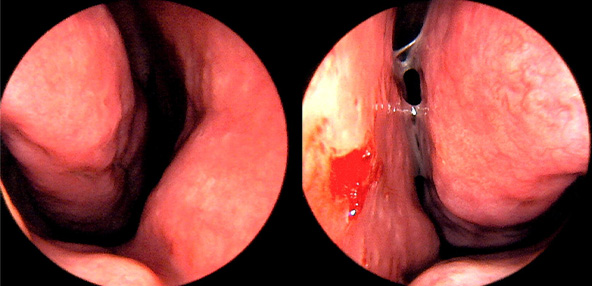

※ 비중격 비염 수술 후 생길 수 있는 부작용으로는 출혈, 감염, 염증이 있을 수 있습니다.

본 사진은 의료기관에서 진료를 본 환자이고, 전후 사진 인물이 동일인이며,동일조건에서 촬영이 되었습니다.